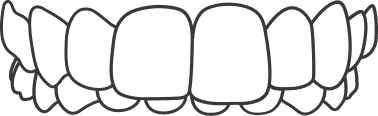

Normally, there should be overlap of 2 mm but when the upper front teeth overlap the lower front teeth for more than 2mm such that they do not touch at all; an overbite is seen.